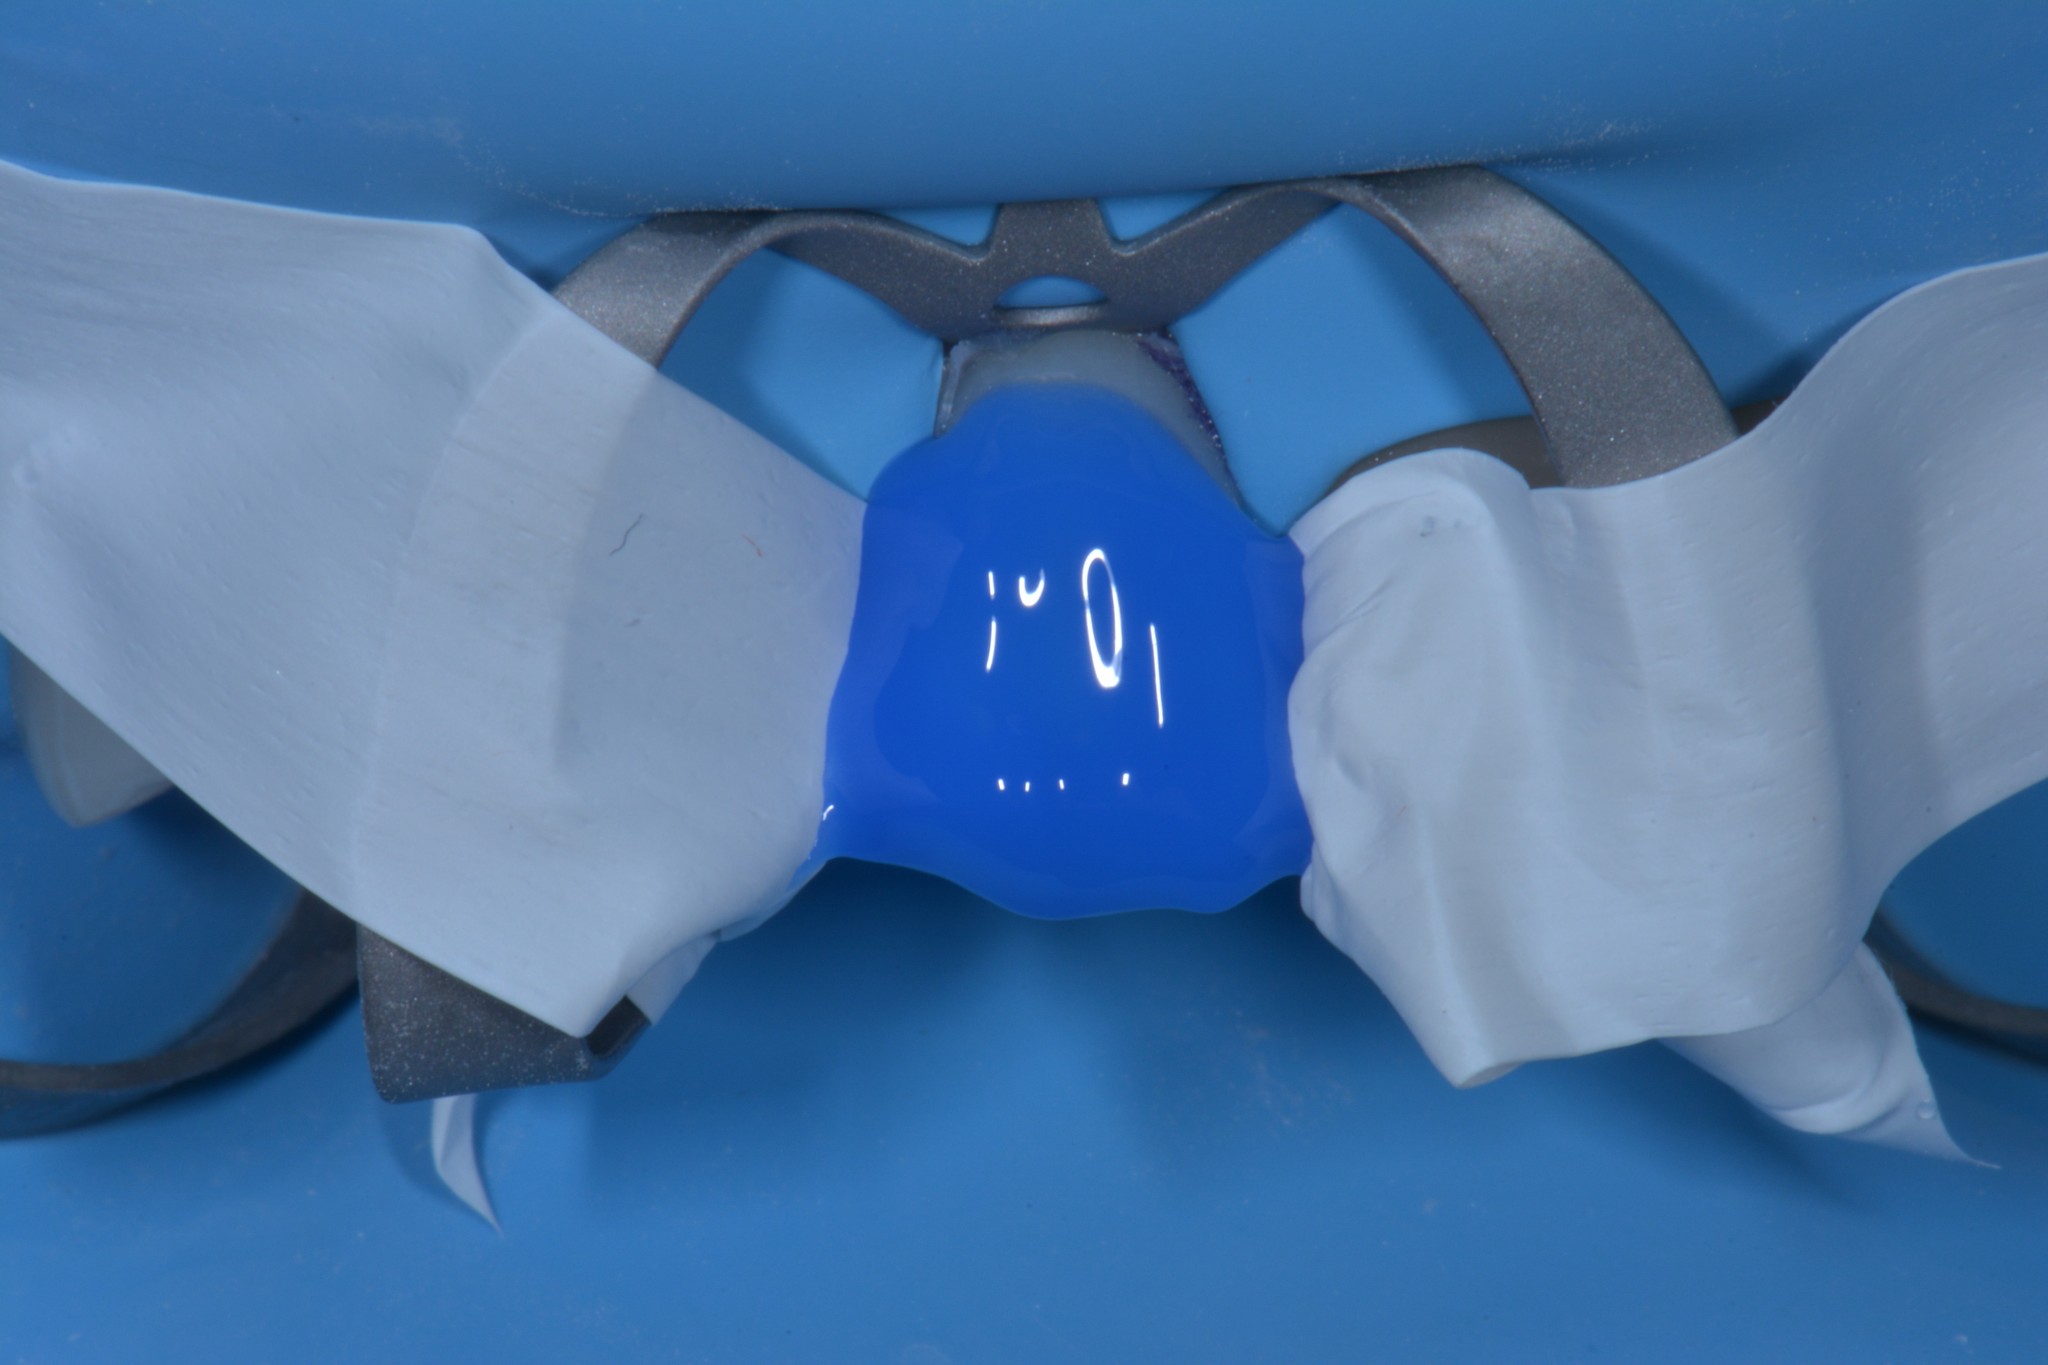

Un altro bellissimo utilizzo per il teflon è lo stampaggio del piano occlusale nelle otturazioni di prima classe (o se ti ingegni anche per le seconde classi) quando il dente da trattare conserva ancora la sua anatomia originale. In questi casi puoi utilizzare del sigillante dei solchi unitamente a del composito flow per creare lo stampo della superficie occlusale, poi, quando arrivi all’ultima applicazione di composito, lo distribuisci a riempimento della superficie occlusale, ci apponi sopra del teflon, premi lo stampo che avevi creato prima di iniziare a preparare la cavità e rimuovi il tutto tirando via il teflon. A questo punto si tratta solo di eliminare gli eccessi di composito e ritoccare leggermente i solchi et voilà! Hai riprodotto una bellissima anatomia che non richiederà praticamente alcun ritocco occlusale in pochi secondi!